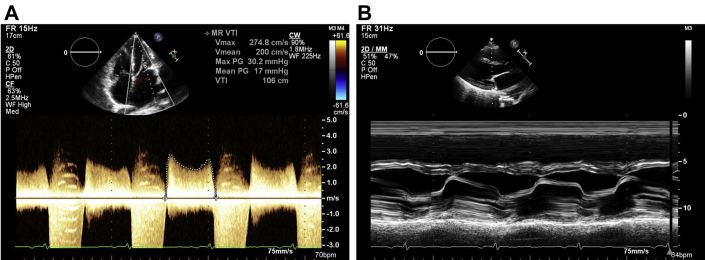

Figure 3.

Transmitral Gradient and M-Mode of Mitral Valve

(A) Mean transmitral gradient 17 mm Hg at a heart rate of 86 beats/min. (B) M-mode of leaflet tips.

The TTE showed severe mitral stenosis with bowing and restriction of the mitral leaflet in parasternal long views (Figure 3, Video 1) and a “fish-mouth” appearance of the mitral orifice, which can be seen in rheumatic valve disease. However, sequential interrogation of the left ventricle in the parasternal short axis revealed hypertrophied papillary muscles with diminutive chordal insertion into leaflet tips and a superiorly displaced anterolateral papillary muscle (Figure 4). There was no evidence of commissural fusion or calcification, which would be more commonly associated with rheumatic valve disease. Left ventricular function was preserved, and right ventricular function was mildly reduced. There was moderate pulmonary hypertension; pulmonary artery systolic pressure (PASP) was 49 mm Hg.